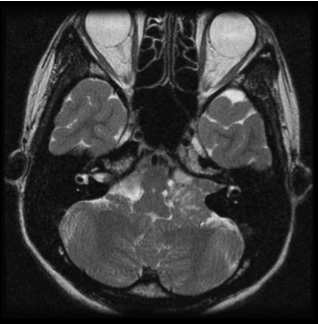

図1:20代男性 聴神経腫瘍

(左図)術前MRI:術前聴力は10dB

(右図)術後MRI:内耳道に筋肉片がおかれている術後聴力は温存16dB 顔面麻痺はなし

図1は若い男性で大きめの腫瘍であったため手術にて摘出しました。術前聴力は良好で、術後もほぼ聴力は変化なく、また顔面神経麻痺も出現していません。